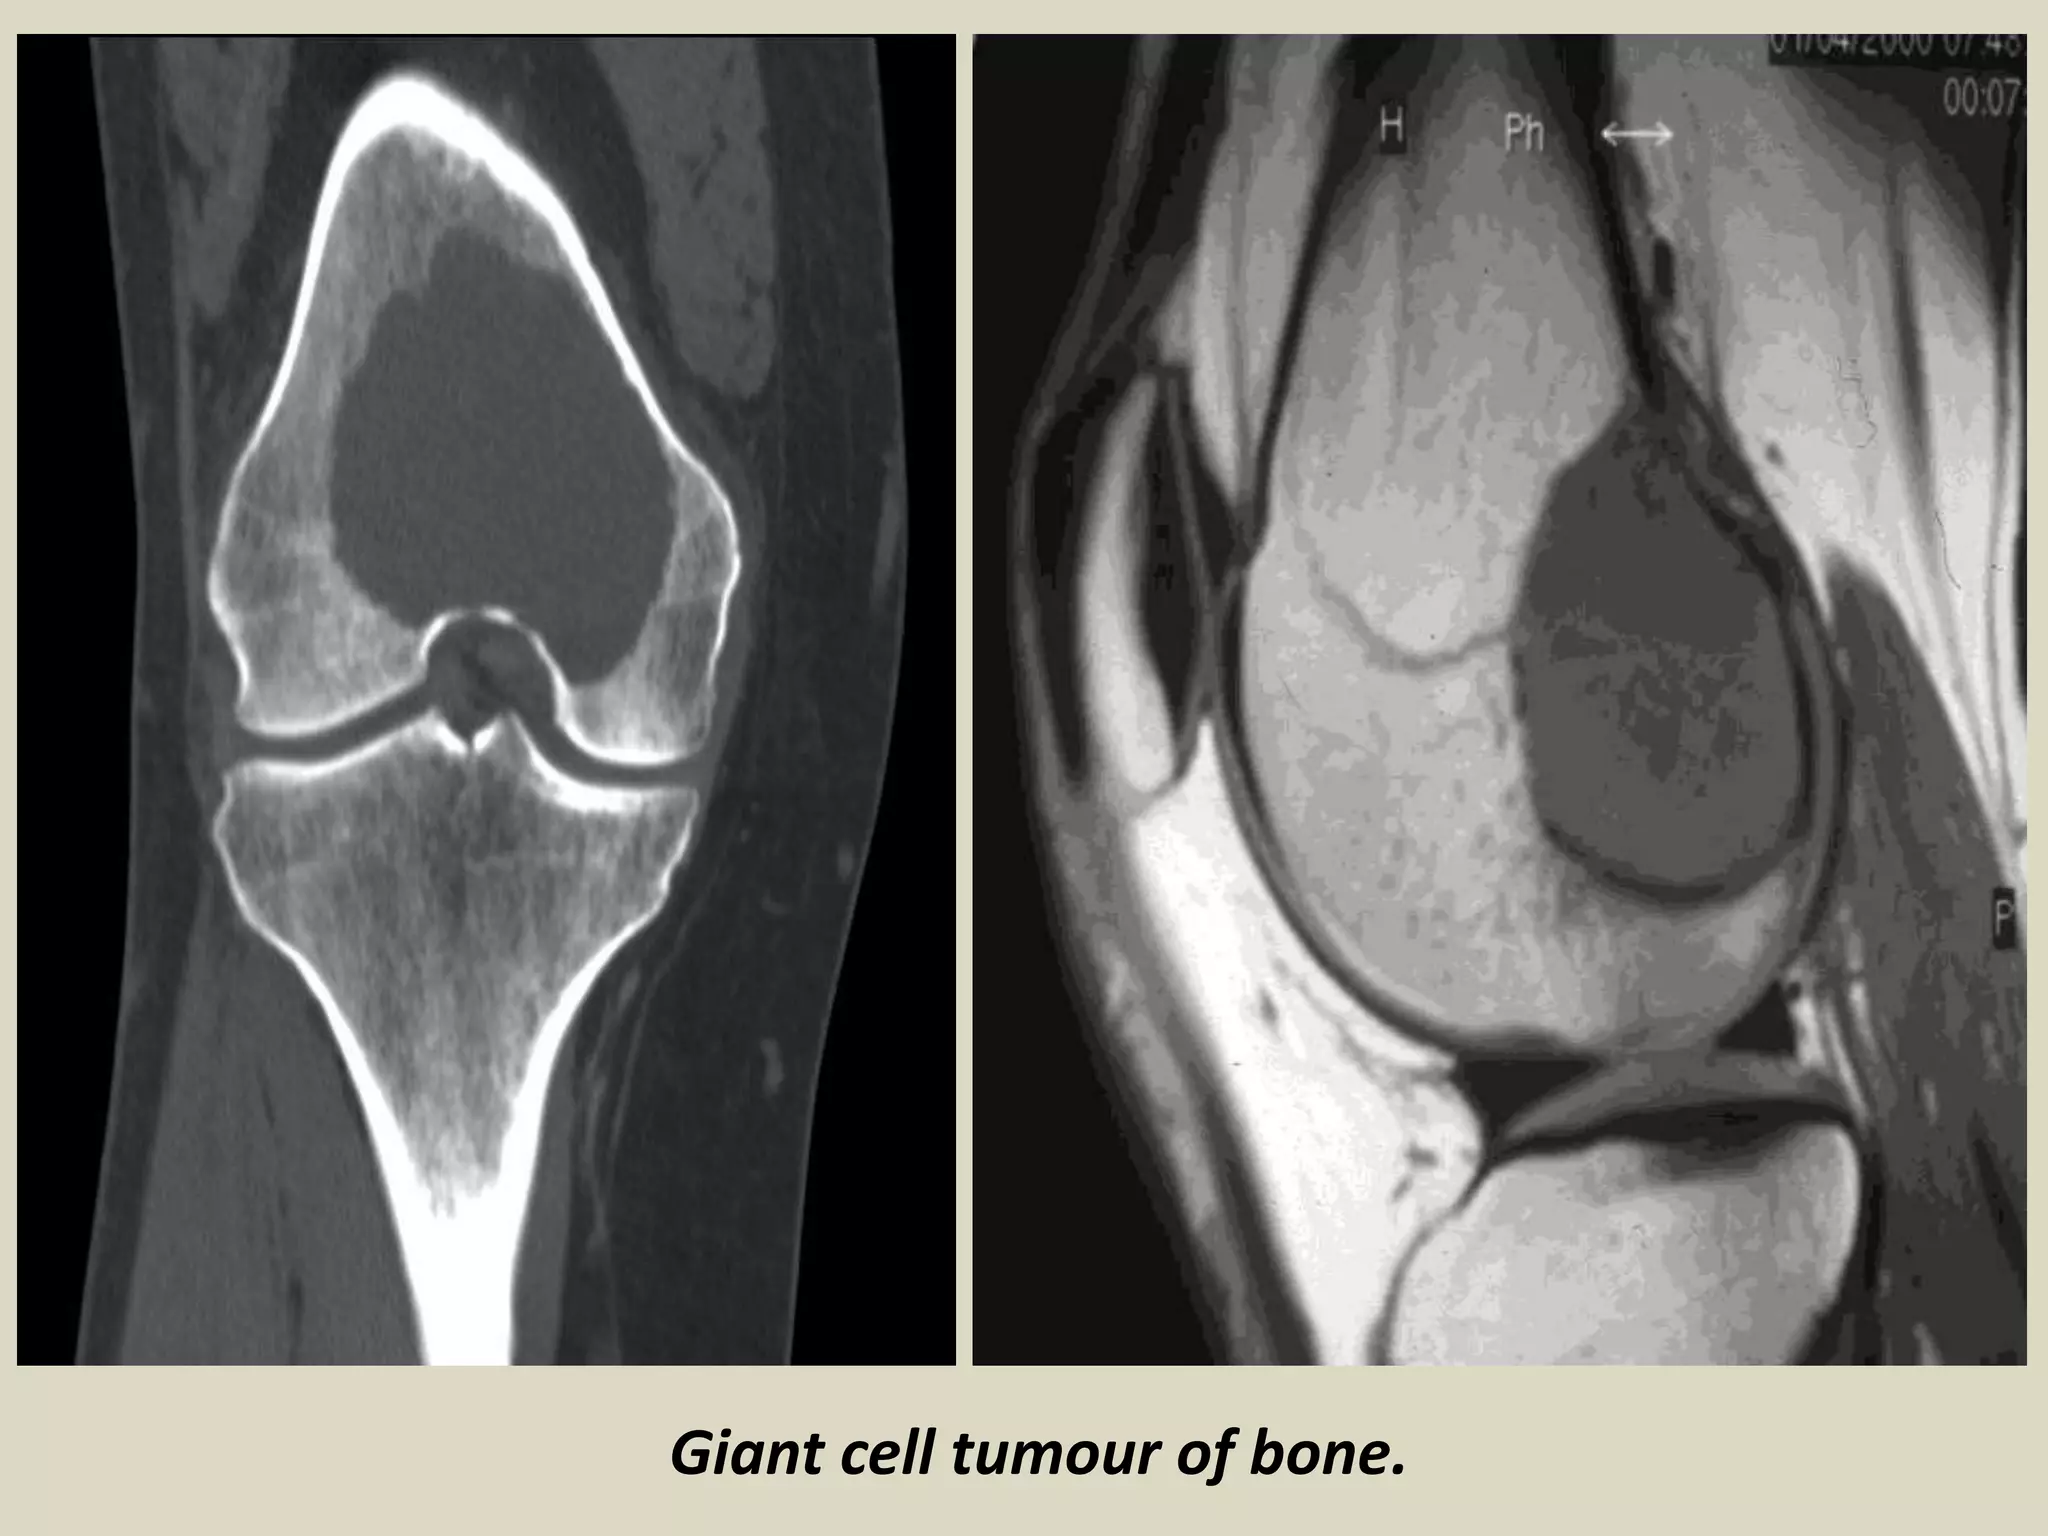

GIANT CELL TUMOR

Definition: Benign, locally aggressive neoplasm.

- Composed of sheets of neoplastic ovoid mononuclear cells interspersed with

uniformly distributed large, osteoclast like giant cells.

Epidemiology:

- Giant cell tumour represents around 4-5% of all primary bone tumours.

- Peak incidence is between the ages of 20 and 45.

- 10-15% of cases occur in the second decade.

- Not commonly seen in adolescents, although cases were described.

- There is slight female predominance described.

Sites of involvement:

- Giant cell tumours typically affect the ends of long bones, especially the distal femur, proximal tibia, distal

radius and proximal humerus.

- About 5% affect flat bones, especially those of the pelvis.

- Multicenteric giant cell tumors are very rare and tend to involve the small bones of the distal extremities.

Clinical findings:

- Patients typically present with pain, swelling and often limitation of joint movement

- Pathological fracture is seen in 5-10% of patients.

Imaging:

- X-rays of lesions in long bones usually show an expanding and eccentric area of lysis.

- Lesion normally involves the epiphysis and adjacent metaphysis.

- Extension up to the subchondral plate, sometimes with joint involvement may be present.

- Rarely, the tumour is confined to the metaphysis, usually in adolescents where the tumour lies in relation

to an open growth plate, but occasionally also in older adults.

- Diaphyseal lesions are exceptional.

- CT scanning gives a more accurate assessment of cortical thinning and penetration than plain radiographs.

Giant cell tumour of bone.